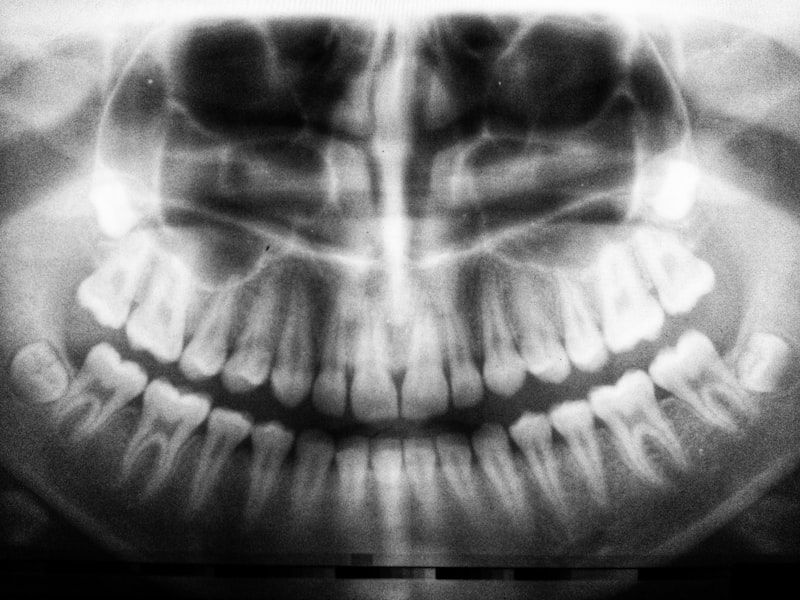

Clinics commonly use digital diagnostics like cone-beam CT (CBCT) imaging, intraoral scanners, CAD/CAM prosthetics, and sterilization protocols that match international standards. These tools improve precision for implant placement, allow better treatment planning, and deliver aesthetic results that meet or exceed expectations.

In Cuenca you’ll find clinics equipped with up-to-date technology: digital x-rays, 3D imaging for bone assessment, guided implant surgery, and on-site laboratories or partnerships for fast, high-quality crowns and veneers. Many clinics operate with an emphasis on infection control, patient comfort, and multi-disciplinary teams (periodontists, prosthodontists, endodontists) to handle complex cases.